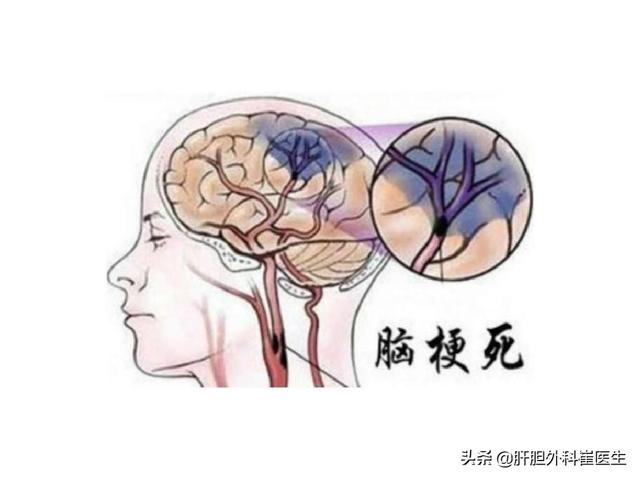

第6 脳血管障害によるもの

特に高齢者では、片腕のしびれや手指のしびれ、手足の脱力を伴う場合には、脳血管障害の発生に注意する必要がある。

4.脳血管疾患

脳血管障害の前駆症状であれ、すでに発症した後の症状であれ、脳血管障害のリスクが高い人にとって、指のしびれは特に注意すべき症状の一つであると言える。ただし、脳血管障害による手指のしびれは、他の症状を伴うことが多く、単独の症状として手指のしびれがみられることもまれではないことを指摘しておく。

まず、脳血管疾患は、指のしびれが原因の脳血管疾患に対して、虚血性脳血管疾患であれば、患者に血行を改善させるだけでなく、栄養神経治療を行うことができ、一般的に患者にイチョウ葉製剤やメチルコバラミン製剤を与えることができます。脳血管障害の急性期であれば、鍼灸治療や漢方薬のイオン導入療法を行うこともできます。

主な問題は、小さな脳梗塞、腫瘍の圧迫、頭蓋内血管奇形の圧迫などである。

一過性脳虚血は手指のしびれの原因として高齢者に多く、特に片側の手足のしびれがある場合に注意が必要である。一過性脳虚血の原因と病態は、脳動脈壁の微小塞栓、脳動脈狭窄に基づく血圧低下、脳血管攣縮などである。上記のような症状が出現した場合には、時間内に病院を受診し、高血圧、高脂血症、高血糖、心房細動などの脳血管障害の危険因子を総合的にスクリーニングし、積極的な予防と治療を行う必要がある。

6.脳梗塞

この病気は、現在、中高年に比較的多い病気で、上肢や手指のしびれが出現することもあり、その原因は、頸動脈圧迫、動脈硬化、脳血栓症などが原因で、脳組織が虚血・低酸素状態になるため、脳神経が障害され、上肢を支配する神経に異常が出現し、それにつながる。